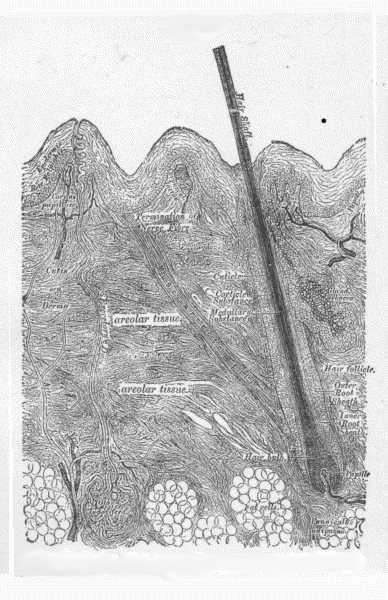

Fig. 1.

Vertical section of the skin—Diagrammatic. (After Heitsmann.)

Fig. 2.

c, corneous (horny) layer; g, granular layer; m, mucous layer (rete Malpighii).

The stratum lucidum is the layer just above the granular layer.

Nerve terminations—n, afferent nerve; b, terminal nerve bulbs; l, cell of Langerhans.

(After Ranvier.)

Fig. 3.

C, epidermis; D, corium; P, papillæ; S, sweat-gland duct.

v, arterial and venous capillaries (superficial, or papillary plexus) of the papillæ.

Deep plexus is partly shown at lower margin of the diagram; vs—an intermediate

plexus, an outgrowth from the deep plexus, supplying sweat-glands, and

giving a loop to hair papilla.

(After Ranvier).

Fig. 4.

a, a vascular papilla; b, a nervous papilla; c, a blood-vessel; d, a nerve fibre;

e, a tactile corpuscle.

(After Biesiadecki.)

Fig. 5.

A, shaft of the hair; B, root of the hair; C, cuticle of the hair; D, medullary substance of the hair.

E, external layer of the hair-follicle; F, middle layer of the hair-follicle; G, internal layer of the hair-follicle; H, papilla of the hair; I, external root-sheath; J, outer layer of the internal root-sheath; K, internal layer of the internal root-sheath.

(After Duhring.)